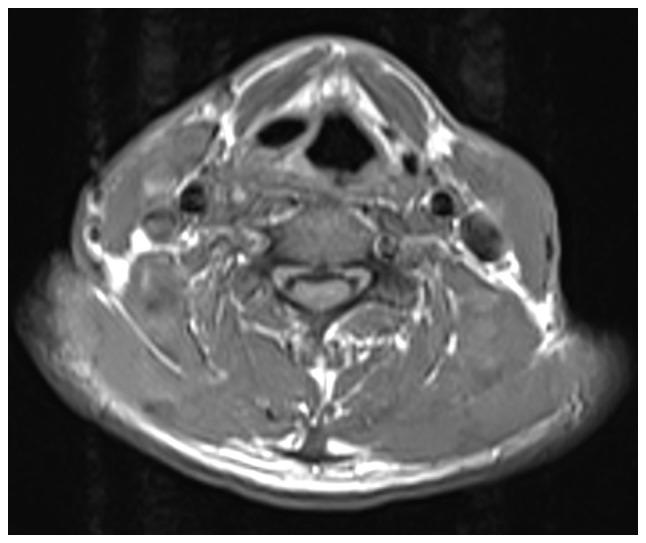

Laryngocele is a rare clinical condition characterized by an abnormal dilation of the laryngeal saccule. The present study focused on two separate cases of diagnosed patients. The first patient suffered from internal laryngocele and complained of hoarseness for almost 1 year. Plasma was used to treat the internal laryngocele and the outcomes were satisfying. The patient did not undergo any tracheostomy due to previous endoscopic surgery. The second patient included in the present study was diagnosed with mixed laryngocele and complained of swelling on the left side of the upper aspect of the neck with considerable pain for >1 month. The patient was prepped for excision by an external transcervical technique under general anesthesia. None of the two patients had any recurrence or other changes during follow-up. The purpose of reporting these two cases of laryngocele was to increase awareness of this condition. Surgery is still the first-line treatment for diagnosed cases, but with the advent of new microscopic techniques, the use of plasma in an inter-pharynx setting has become more common. The results observed after using plasma to treat one internal laryngocele may be relevant to better understanding the application of this method and confirm that it may be a new suitable approach to treat this condition.

喉膨出是一种罕见的临床病症,其特征为喉囊异常扩张。本研究聚焦于两例确诊患者。首例患者患有内喉膨出,主诉声音嘶哑近1年。采用等离子体治疗内喉膨出,效果令人满意。由于先前的内镜手术,该患者未进行任何气管切开术。本研究纳入的第二例患者被诊断为混合型喉膨出,主诉颈部上方左侧肿胀并伴有明显疼痛超过1个月。该患者在全身麻醉下通过外部经颈技术准备进行切除术。两名患者在随访期间均未出现任何复发或其他变化。报告这两例喉膨出病例的目的是提高对该病症的认识。手术仍然是确诊病例的一线治疗方法,但随着新的显微技术的出现,等离子体在咽内环境中的应用变得更加普遍。使用等离子体治疗一例内喉膨出后观察到的结果可能有助于更好地理解该方法的应用,并证实它可能是治疗这种病症的一种新的合适方法。